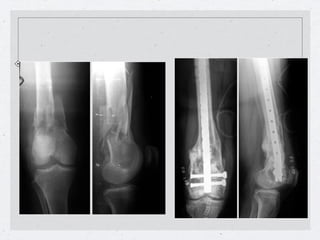

Enclavado Retrógrado

en las fracturas distales de fémur

Introducción del clavo en el espacio intercondíleo de la rodilla.

Enclavado Retrógrado en las fracturas distales de fémur Introducción del clavo en el espacio intercondíleo de la rodilla.